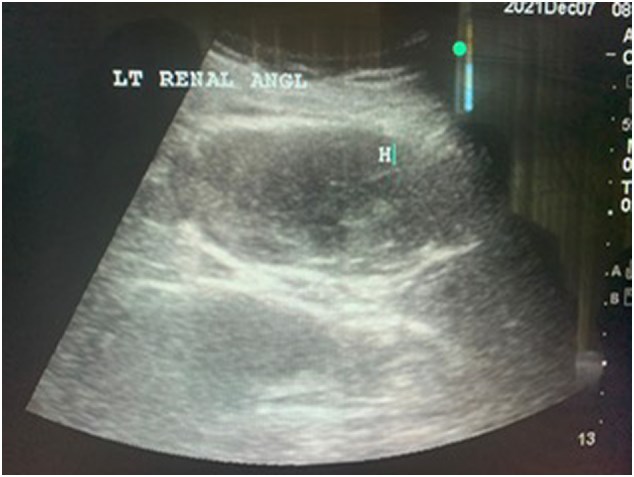

Case presentation: We present the case of a 74-year-old male with ischemic heart disease on dual antiplatelet. He developed vague abdominal pain and hemoglobin drop without overt bleeding source until he developed shock. Modified POCUS examination that included the retroperitoneal space detected the bleeding source and confirmed later by computerized tomography of the abdomen. The case was managed conservatively.

Clinical discussion: The risk factors associated with the formation of spontaneous retroperitoneal hematomas are age above 70 years and dual antiplatelet therapy. The initial integration of point-of-care ultrasound into the assessment of shocked patients leads to an earlier and accurate initial diagnosis with a clear patient care plan. POCUS should include the retroperitoneal space examination in every patient presenting with shock.

Conclusion: In patients with unexplained hemorrhagic shock, a modified POCUS protocol could help by including an examination of the retroperitoneal space in the assessment.